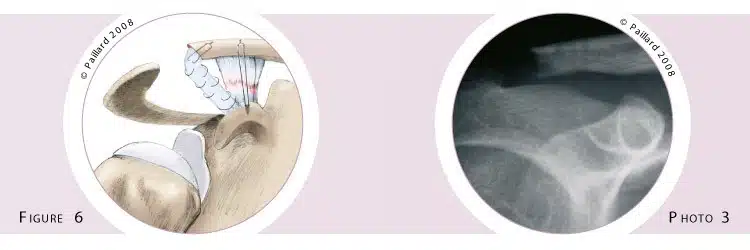

If the surgery is performed some time after the trauma, the ligaments will no longer have the ability to heal. It will therefore be necessary to reposition the collarbone and replace the ruptured ligaments with a new ligament; this is “ligament reconstruction”. It often requires a short incision in the front of the shoulder, but can sometimes be performed arthroscopically. In addition to a simple stabilization with a system of resistant threads between the collarbone and the coracoid, the ligaments are replaced. To do so, the extremity of the collarbone is cut (figure 5). The arcomioclavicular ligament, which is an accessory ligament stretched between the coracoid and the acromion, is detached from the latter. It is then fixed in the cut made in the collarbone, thus replacing the ruptured ligaments (figure 6, photo 3).